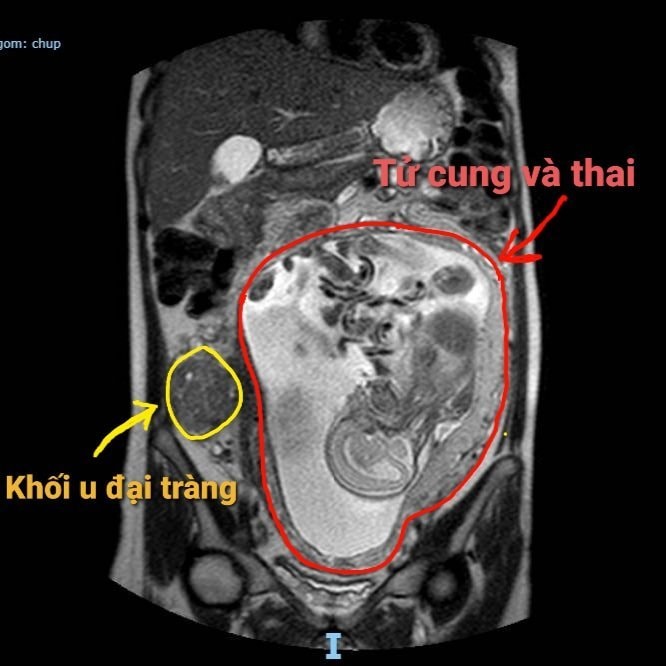

Trước đó, Bệnh viện Đà Nẵng tiếp nhận bệnh nhân Nguyễn D.T. (SN 1992), ngụ quận Thanh Khê, đang mang thai con đầu lòng ở tuần thứ 21. Bệnh nhân cảm thấy đau bụng âm ỉ vùng hố chậu phải, sờ thấy một khối gồ lên tại vị trí này nên nhập viện. Qua thăm khám lâm sàng kết hợp với các xét nghiệm cận lâm sàng, các bác sĩ phát hiện khối u manh tràng kích thước khoảng 5×6cm.

Sau đó, bệnh nhân được hội chẩn liên chuyên khoa gồm khoa Ngoại tiêu hóa, Gây mê hồi sức, Sản, Ung bướu, Chẩn đoán hình ảnh và Dược lâm sàng. Và được chỉ định phẫu thuật nội soi cắt đại tràng phải. Mặc dù thai lớn quá rốn gây khó khăn cho việc thực hiện các thao tác nhưng ca mổ vẫn có thể tiến hành bằng phẫu thuật nội soi, khối u được lấy ra ngoài qua một đường rạch da nhỏ tại rốn. Ca phẫu thuật được thực hiện trong khoảng 3 giờ đồng hồ.